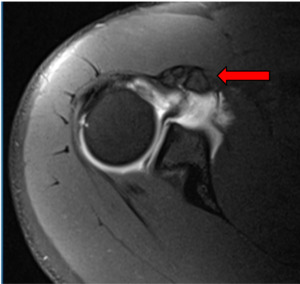

Imaging: Preoperative imaging included standard radiography using anteroposterior, Grashey, scapular Y and axillary views (Fig 1-2). After determining the presence of a coracoid fracture, advanced imaging was conducted via computed tomography with addition of 3-dimensional reconstruction. CT imaging was suggestive of a type 2 coracoid fracture nonunion (Fig 3) which was then further verified with no enhancement with T2 MRI sequences (Fig 4).